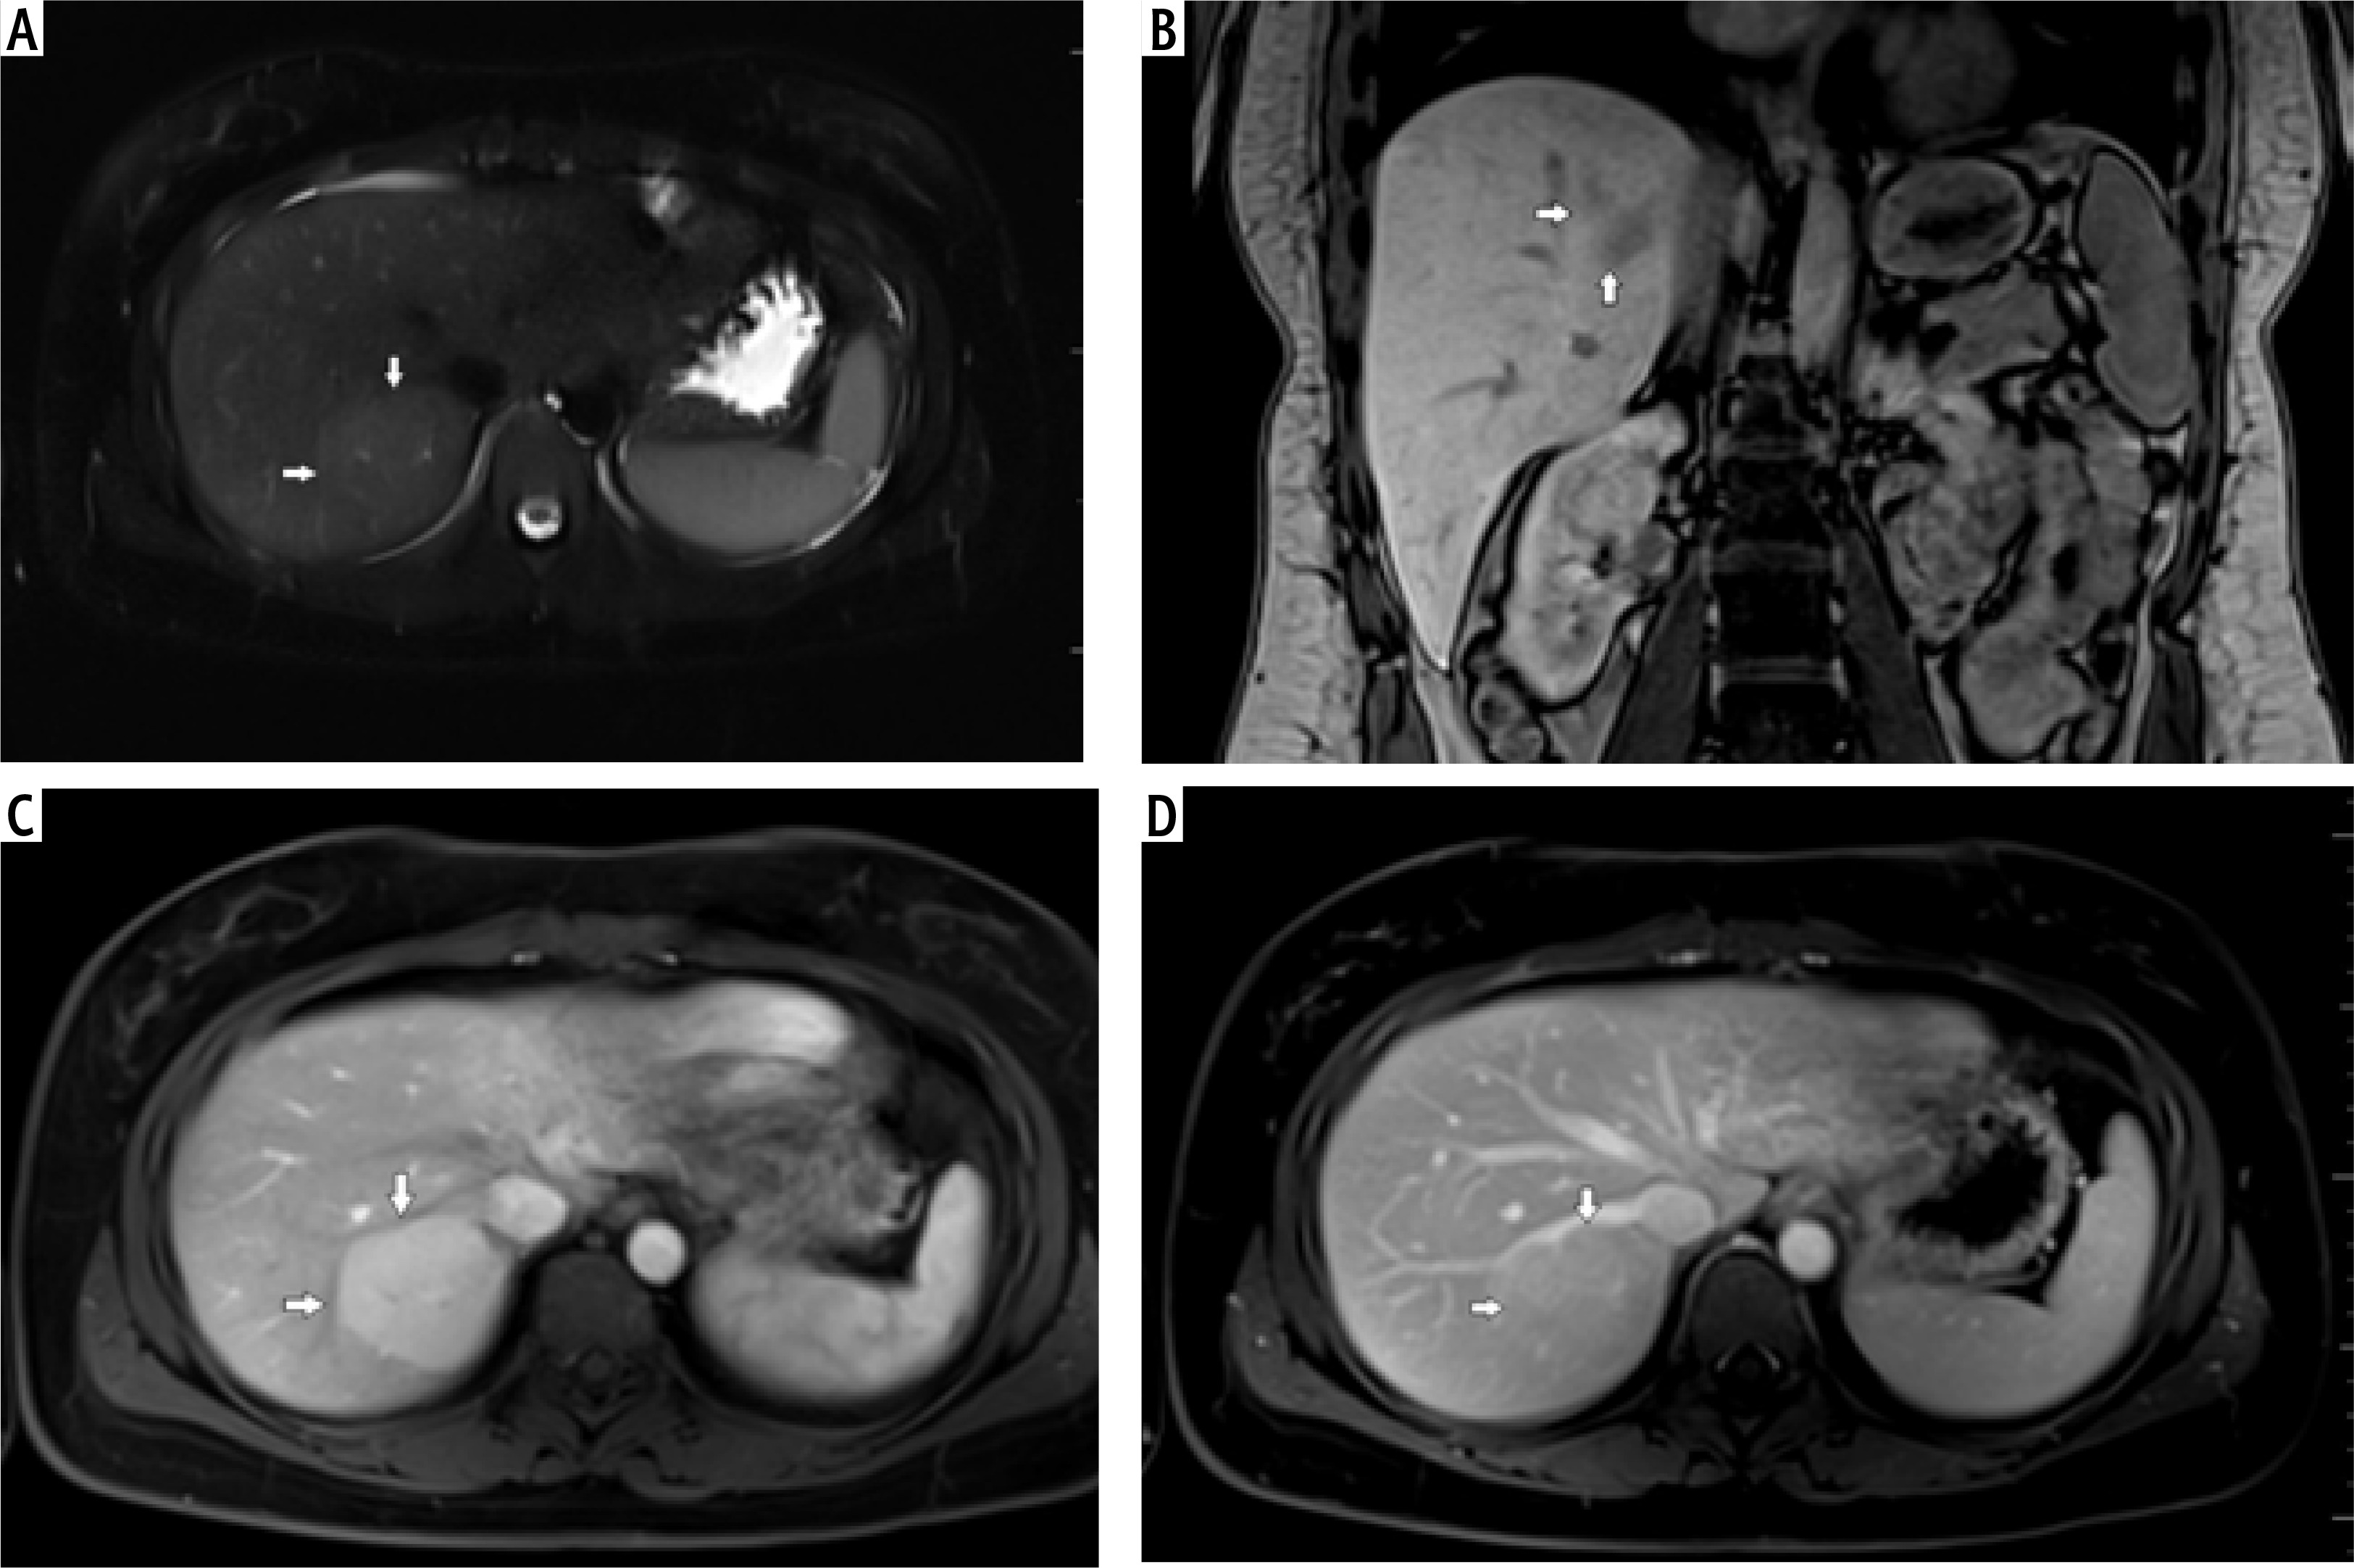

Fig. 1

A) T2-weighted image in transverse plane, focal lesion in right lobe of liver (full white arrows). Signal of lesion slightly higher in relation to the liver parenchyma. In the central part, a small area with lower signal (empty white arrow). B) T1-weighted image in coronal plane, focal lesion in right lobe of the liver (full white arrows). The lesion signal is lower in relation to the liver parenchyma. In this sequence, a well-visible hyposignal central fibrous scar and spoke spaced connective tissue septa are clearly visible. C) T1-weighted image at an early stage after administration of contrast agent. Acquisition in the transverse plane, focal lesion in the right lobe of the liver (full white arrows). The lesion is enhanced intensively in relation to the liver parenchyma. Hyposignal scar remains in the center of the lesion. D) T1-weighted image in the late phase after administration of contrast agent. Acquisition in transverse plane. Focal lesion in the right lobe of the liver (full white arrows). Enhancement of the lesion and the liver parenchyma in this phase is similar. Lesion was qualified as focal nodular hyperplasia (FNH)